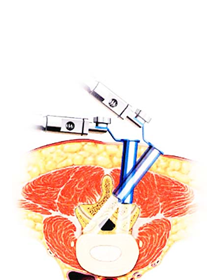

XLIF®(エックスリフ)

eXtreme Lateral Interbody Fusion(XLIF®/エックスリフ)は、脇腹からの小皮切で腰椎に側方からアプローチし、脊椎前方に十分な骨移植を行ない脊椎の矯正固定を行なう手術技術です。椎間板変性や脊椎椎体骨折に伴う脊椎後側彎症(腰曲がり)、椎間不安定性を有する腰部脊柱管狭窄症で固定術を必要とする場合などが手術適応となります。手術にあたってはレントゲン透視画像と神経刺激モニターを用いて重要な神経へのダメージを回避します。出血が従来に比べ非常に少なく、体への負担が少ない手術方法です。和歌山県立医科大学整形外科では2013年に山田宏教授が全国に先駆けてXLIFを導入し、以来200例以上の手術実績(2017年7月現在)があります。原則、手術翌日より起立・歩行を開始します。手術後は硬いコルセットを装着します。入院期間は病態により異なりますが、概ね2-4週間です。

eXtreme Lateral Interbody Fusion(XLIF®/エックスリフ)は、脇腹からの小皮切で腰椎に側方からアプローチし、脊椎前方に十分な骨移植を行ない脊椎の矯正固定を行なう手術技術です。椎間板変性や脊椎椎体骨折に伴う脊椎後側彎症(腰曲がり)、椎間不安定性を有する腰部脊柱管狭窄症で固定術を必要とする場合などが手術適応となります。手術にあたってはレントゲン透視画像と神経刺激モニターを用いて重要な神経へのダメージを回避します。出血が従来に比べ非常に少なく、体への負担が少ない手術方法です。和歌山県立医科大学整形外科では2013年に山田宏教授が全国に先駆けてXLIFを導入し、以来200例以上の手術実績(2017年7月現在)があります。原則、手術翌日より起立・歩行を開始します。手術後は硬いコルセットを装着します。入院期間は病態により異なりますが、概ね2-4週間です。